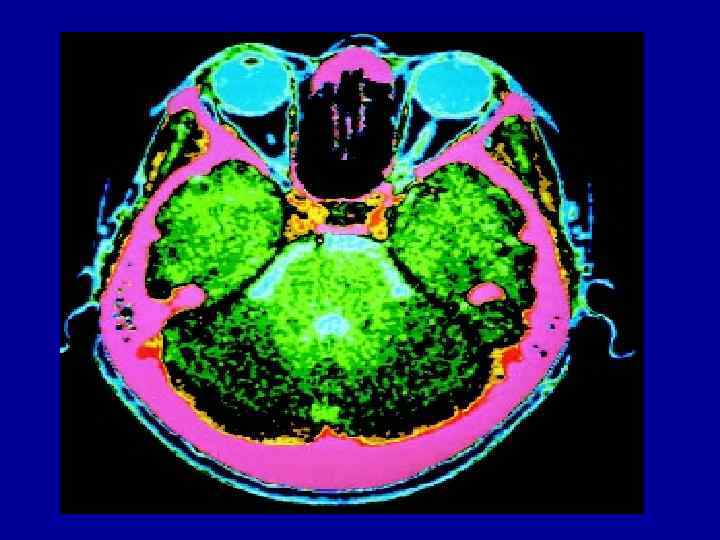

Методы изучения топографической анатомии 1. Послойное препарирование 2. Препарирование через окончатые разрезы 3. Наливки Методы изучения топографической анатомии 1. Послойное препарирование 2. Препарирование через окончатые разрезы 3. Наливки контрастными веществами 4. Методы прижизненного исследования: рентгеноскопия, УЗИ, компьютерная томография, термография и т. д.